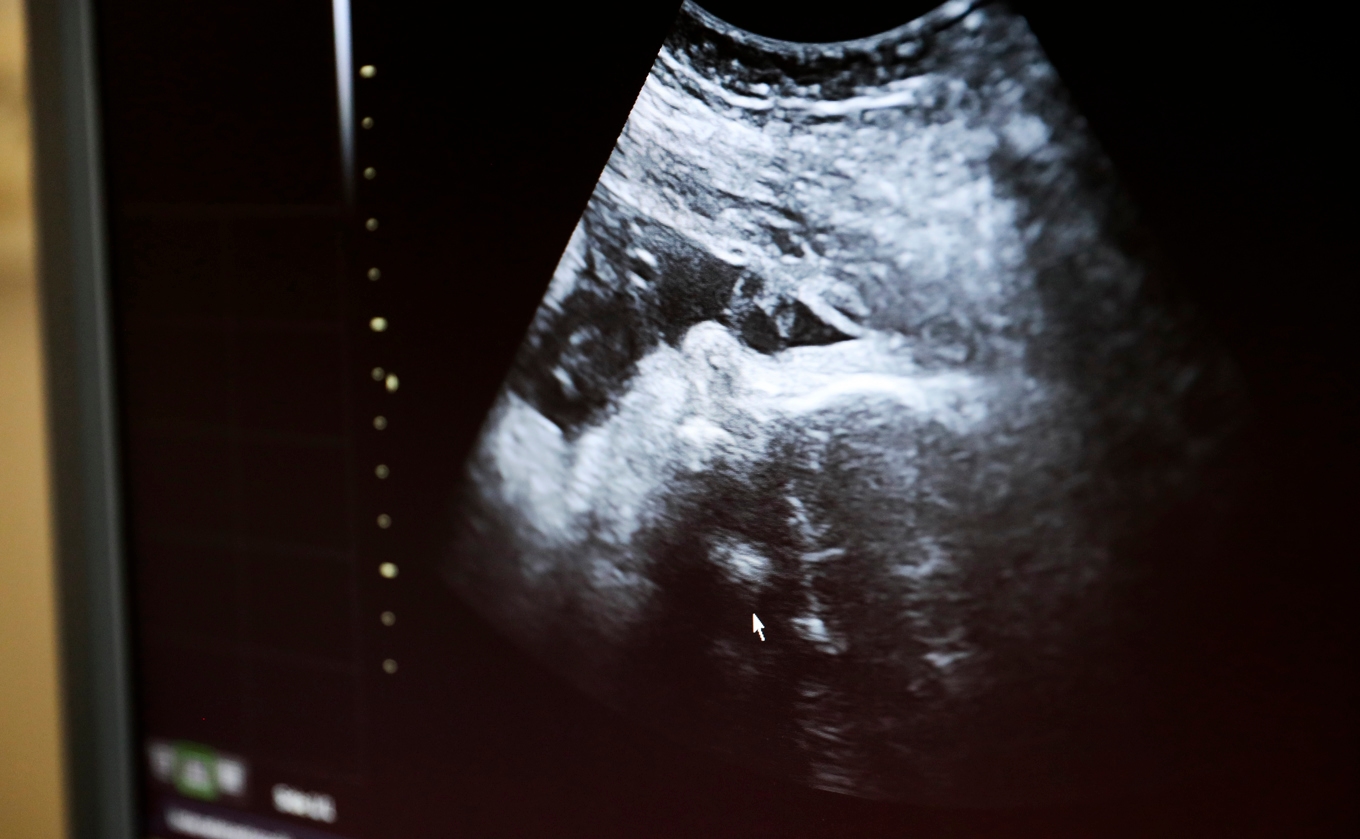

Enligt en SVT-undersökning planerar flera regioner att ersätta kub med det mer träffsäkra NIPT. Kub används i dag för att undersöka sannolikheten för kromosomavvikelser hos fostret. När kub visat på en avvikelse används ofta NIPT som uppföljning.